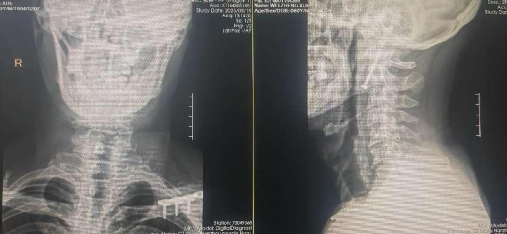

患者韦某某,男性,60岁,因高处坠落至颈部疼痛,来到我院脊柱外科就诊。经详细影像学检查,诊断为II型枢椎齿状突骨折。在与家属充分沟通并经过周密的术前准备,通过脊柱外科副主任、博士研究生、主任医师张鹭的指导和麻醉与围术期医学科和脊柱外科医护人员的通力配合下,手术顺利进行。术中首先在透视下进行牵引复位,再通过术中可移动3D C臂对患者骨折部位进行扫描,然后在电脑中模拟规划螺钉植入的位置,利用手术机器人机械臂进行导航精准植入1枚齿状突拉力螺钉,使患者的骨折得到良好的复位固定。张鹭表示:前路骨折固定的优点是能够调整患者保持C1~C2的活动度,大概占颈椎旋转功能的50%,另一优点为骨折融合率为80%~95%。目前,在骨科机器人的辅助下,可利用机械臂精准导入从颈椎前方进行螺钉固定,具有创伤相对小、恢复快的特点,使手术更加精准、稳定,保证了手术的安全性。

术前影像学检查

术后第2天,患者佩戴头颈胸支具即下地自由活动,复查时CT证实螺钉的位置理想。